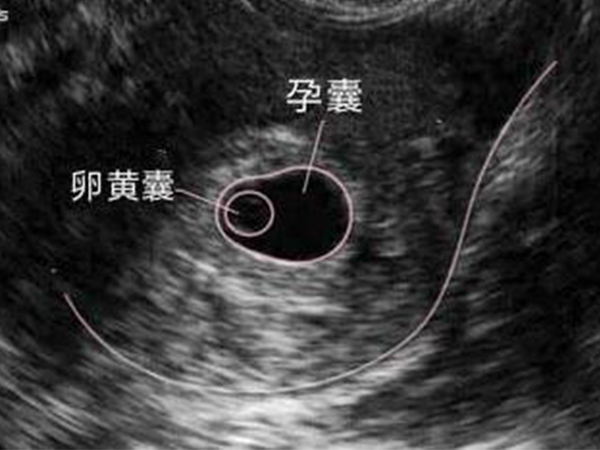

卵黄囊是胎儿发育的一个重要阶段,一般是怀孕5~6周时出现,是早期孕囊的一个标志,因此卵黄囊十分重要。卵黄囊在发育过程中,每天都会发生变化,怀孕的天数不同,卵黄囊的大小也不同,不同怀孕天数的卵黄囊大小都有一个对照标准,如果不在这个范围内就说明存在异常。

卵黄囊是孕囊发育的一个重要阶段,是胚芽形成前的存在形式,对胎儿的发育十分重要,如果卵黄囊出现任何异常,都说明胎儿发育出现异常,因此在怀孕期间一定要重视卵黄囊的出现及其大小变化,同时要做好各种注意事项和保护措施,尽量给胎儿一个发育的良好环境。

卵黄囊一般是5~6周出现,然后12周左右消失,而卵黄囊的大小在3~5毫米之间,最大不会超过8毫米。同时,卵黄囊的大小和怀孕时间有一个对照标准,对照表数据如下:

4周28天左右,胎儿只有0.2厘米,受精卵刚完成着床,羊膜腔才形成,卵黄囊出现,体积很小;5周35天左右,胎儿长到0.4厘米,进入了胚胎期,羊膜腔扩大,原始心血管出现,可有搏动;6周42天左右,胎儿长到0.85厘米,胎儿头部、脑泡、额面器官、呼吸、消化、神经等器官分化;7周49天左右,胎儿长到1.33厘米,胚胎已具有人雏形,体节已全部分化,四肢分出,各系统进一步发育;8周56天左右,胎儿长到1.66厘米,胎形已定,可分出胎头、体及四肢,胎头大于躯干;9周63天左右,胎儿长到2.15厘米,胎儿头大于胎体,各部表现更清晰,头颅开始钙化、胎盘开始发育;10周70天左右,胎儿长到2.83厘米,胎儿各器官均已形成,胎盘雏形形成。B超可见胎囊开始消失,月芽形胎盘可见,胎儿活跃在羊水中;11周77天左右,胎儿长到3.62厘米,胎儿各器官进一步发育,胎盘发育。B超可见胎囊完全消失,胎盘清晰可见;12周84天左右,胎儿长到4.58厘米,外生殖器初步发育,如有畸形可以表现,头颅钙化更趋完善,卵黄囊逐渐被吸收,逐渐消失。

上述就是卵黄囊出现后,对应时间应该有的大小,如果在这个大小范围内有偏小情况的话,也属于比较正常的情况,因为个体存在差异,可能存在出现偏晚的情况,但是如果其大小有较大的差异,那么就说明胎儿发育存在异常,需要重视!